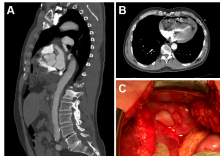

[3]Figure 1. (A) Sagittal CT image showing diaphragmatic defect with small bowl herniated into the pericardium. (B) Axial CT image showing intrapericardial loop of small bowel compressing the chambers of the heart causing cardiac tamponade. (C) Photographic image of the defect in the diaphragm after reduction of intestinal contents.

Two and a half years later, the patient presented with acute onset of severe epigastric pain and associated nausea and vomiting. Concern for possible aortic dissection prompted a computed tomography angiogram of the chest, which revealed the small bowel herniated through the diaphragmatic defect with ventricular compression. Although initially stable, the patient became hemodynamically unstable during transfer and on arrival was on multiple vasopressors. His abdomen was rigid with peritoneal rebound tenderness. Initial laboratory evaluation revealed an arterial pH of 7.04 with a base deficit of 17, an anion gap of 21, and lactate of 8.4. He was taken emergently to the operating room for exploratory laparotomy. Reduction of the herniated small bowel through the diaphragmatic defect from the CP resulted in immediate restoration of normal hemodynamics. A 20 cm in length of infarcted jejunum was resected and primarily reconstructed. The 2 cm defect in the central tendon of the diaphragm could not be approximated primarily due to tension. Because of the potential contamination from the infarcted small bowel, the falciform ligament was secured in a circumferential fashion over the defect with a running 2-0 Prolene® suture. The patient did well postoperatively and was discharged home six days later.